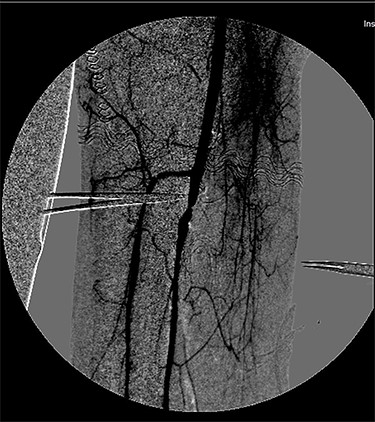

An emergency vascular surgery consultation was required. Upon our arrival, the foot was hypothermic and pale, with pain and paraesthesia. At the angiography, near occlusion of the SFA at its middle third was found, with concomitant occlusion of the popliteal artery and of the leg arteries (Fig. 2).

ONYX 34 residuals in the distal popliteal artery and in the tibioperoneal trunk obstructing blood-flow in the right lower limb.